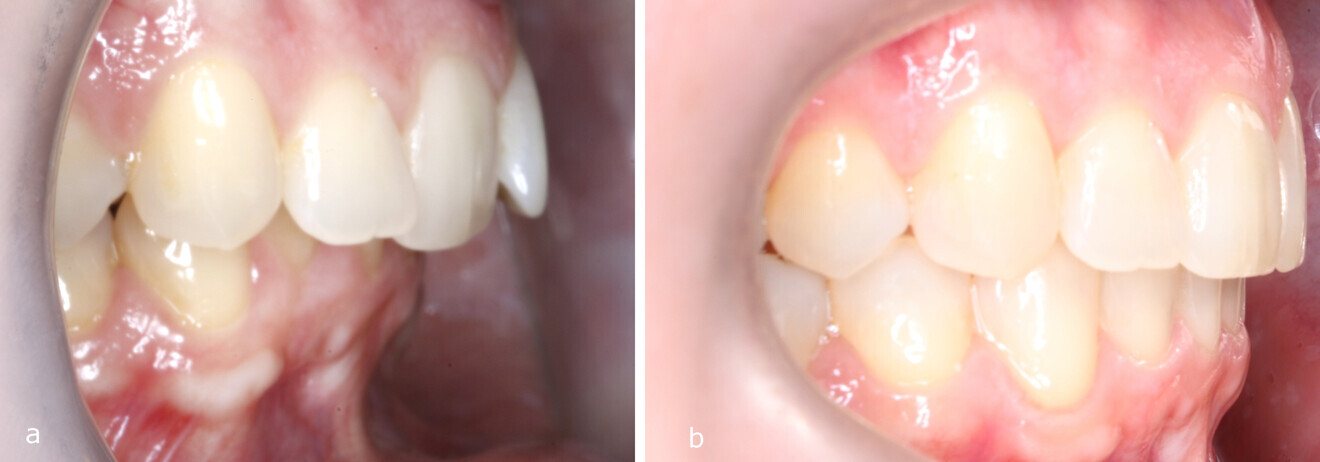

Figs. 9a & b: Overjet before and after the treatment.

The first sequence of aligner treatment consisted of 62 aligners, followed by ten aligners for refinement. During the course of treatment, the posterior teeth were asymmetrically distalised on both sides, anterior crowding in the maxillary and mandibular arches was resolved, the sagittal discrepancy was reduced and the midline deviation was corrected (Figs. 8 & 9). Afterwards, the patient wore vertical elastics for two months to achieve settling in the molar region. The total active treatment duration was 19 months.